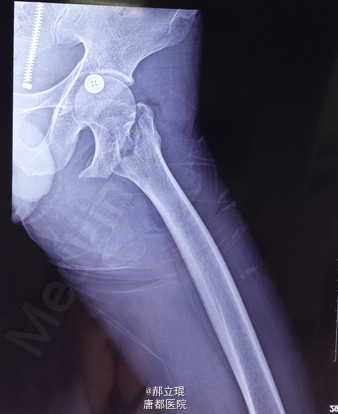

股骨颈基底部

术后十天出院,不再疼痛。建议多吃高钙产品。四个月后老人基本能够活动,每天能坚持锻炼。